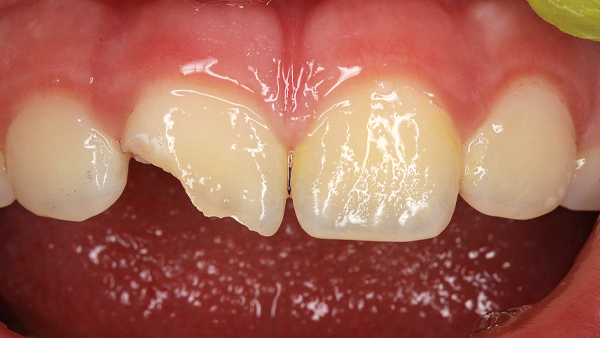

Daimi dişlərin travmatik zədələnmələri uşaq və yeniyetməlik dövründə olan şəxslərdə çox tez-tez rast gəlinir. Tac qırılmaları və lüksasiya travmalar içərisində ən çox rast gəlinənlərdir. Ancaq müxtəlif kliniki hallarda digər zədələnmə formaları da aşkar edilə bilir.